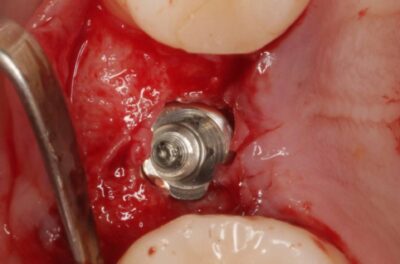

Специализация: терапия(эндодонтия), ортопедия, имплантология.